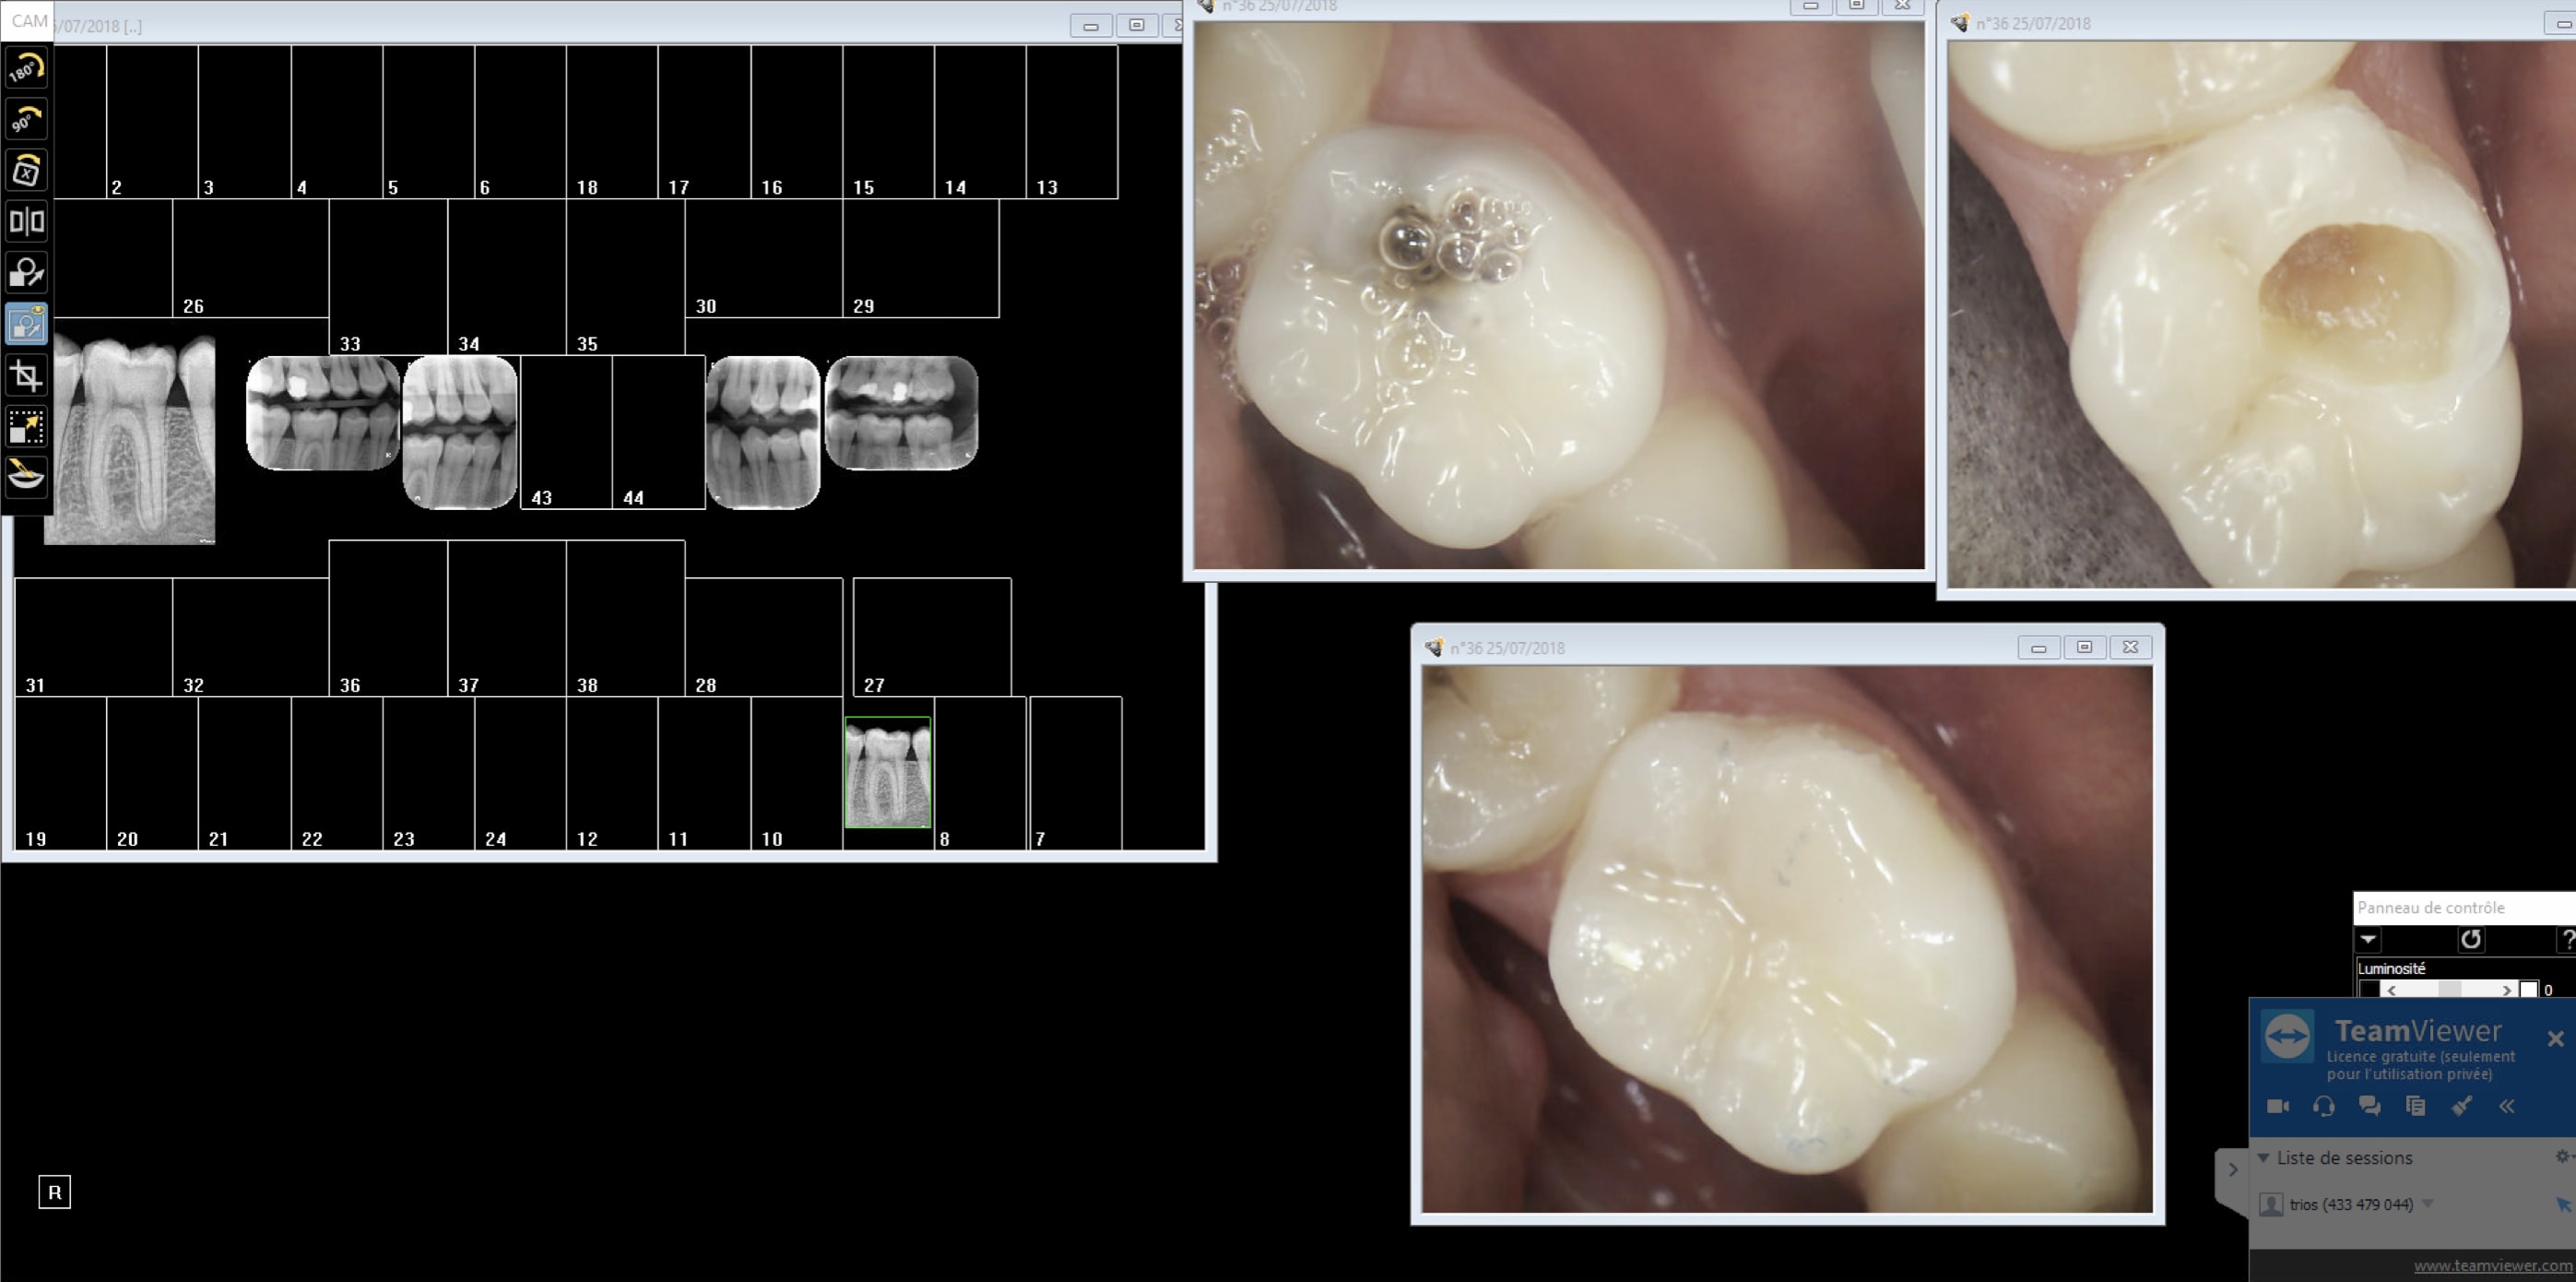

Exemple nouveau patient consulte pour problème sur 36. 1 radio rétroalvéolaire 36 indication carie pénétrante(capteur) , 2 anesthésie 3 rétrocoronaires indication : recherche de caries ( plaques) 4 compo 36.

Capture d écran 2018 07 25 14.14 - Eugenol

Regardes moi la qualité de merde que ca te sort un système à plaques. C'est completement inconstant. Il n'y a pas photo. -)))

Capture d écran 2018 07 25 14.22 - Eugenol

Le comparatif de mire de cyber_, quand meme, c'est un peu plus rigoureux. Tu prends tes angulations differentes, on ne connait pas l'etat de ta plaque, les deux systemes ont ils le meme age?

Le stratagème est gros ! Tu nous montres un cliché de capteur rétroalvéolaire , avec une accentuation de netteté logiciel au maximum, d'un côté, avec un cliché rétrocoronaire d'une plaque pourrie ( cf défauts de surface), sans accentuation de netteté !!

+1 sur la plaque ruinée...

OK une autre plaque faut jouer avec les filtres avec le capteur non. Ca se ruine assez vite les plaques et ça vaut la peau du derche. Excuses moi le capteur est plus vieux de 5 ans que ces plaques de merde.

Capture d écran 2018 07 25 20.21 - Eugenol

C'est un constat plaques vieilles ou pas plus de boulot à tirer un cliché valable ( gestion du temps d'expo par ex, faire gaffe à ce qu'elles ne prennent pas la lumière au développement ensacheter dés-ensacheter). Le capteur c'est 0,09 s de temps d'exposition point barre. J'ai les 2 bordel pour moi il n'y a pas photo. Faut pas acheter des capteurs de merde non plus. Quand t'en fais 2 dans ta journée tu peux t'appliquer mais quand t'en fais 50 ca commence à etre casses burnes. -)))